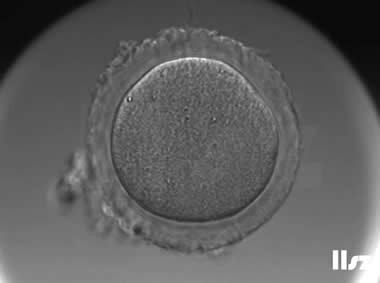

2. 不成熟卵母细胞(MI)及其COCs

卵细胞颜色变浅,放射冠开始分散,颗粒细胞排列逐渐稀疏,颜色亦变浅,不可见GV和第一极体。不成熟卵母细胞的核成熟时间可以发生在体外培养15个小时以内。

|  |

| 0小时COCs的MI卵(4x) | 0小时COCs的MI卵(10x) |

|  |

| 2小时COCs的MI卵(10x) | 4小时去颗粒细胞后的MI卵(10x) |